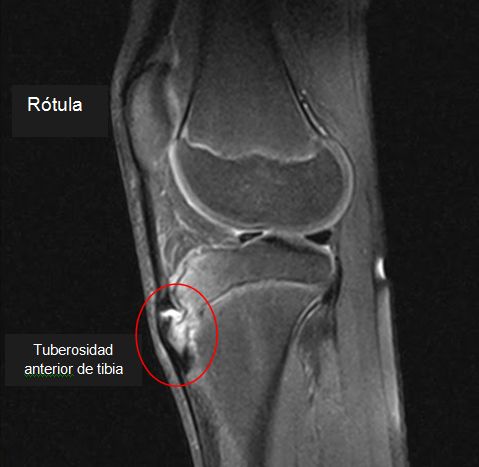

DOLOR EN MIEMBROS INFERIORES.

SEMIOLOGIA DE LOS MIEMBROS INFERIORES